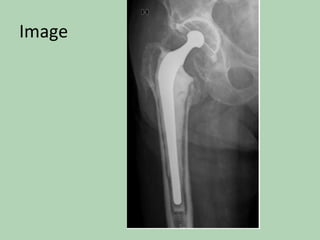

Diagnosis:

Clinical

Image